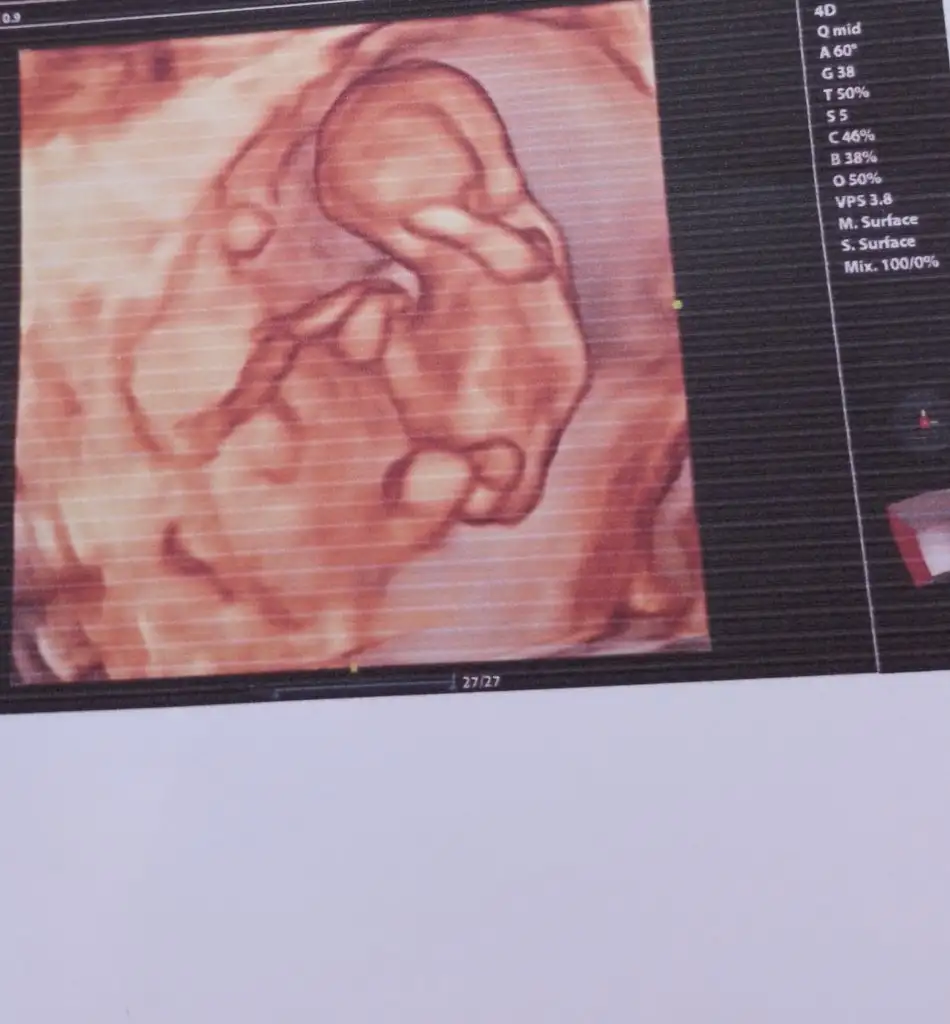

Allah sağlıkla gelmesini nasip eylesinDoktorum da öyle dedi bu ay gittiğimde kesin netlik kazanacak bakalım

Kızlar bugün kontrolüm vardı şuan 12.haftamın içindeyim 2 li tarama yapıldı ama cinsiyetine erken olduğu için doktor bir şey demedi. Bir ay sonraya çağırdı gerçekten merak ediyorum tecrübeli olanlar varsa tahmin edebilir miBi de 2 gün geç döllenme olmuştu başta ama şuan 1 gün önden gidiyormuş belki işinize bana da yorum yaparmisiniz bende çok merak ediyorum

Bana da yorum yaparmisiniz bende çok merak ediyorumKızlar bugün kontrolüm vardı şuan 12.haftamın içindeyim 2 li tarama yapıldı ama cinsiyetine erken olduğu için doktor bir şey demedi. Bir ay sonraya çağırdı gerçekten merak ediyorum tecrübeli olanlar varsa tahmin edebilir miBi de 2 gün geç döllenme olmuştu başta ama şuan 1 gün önden gidiyormuş belki işinize yarar